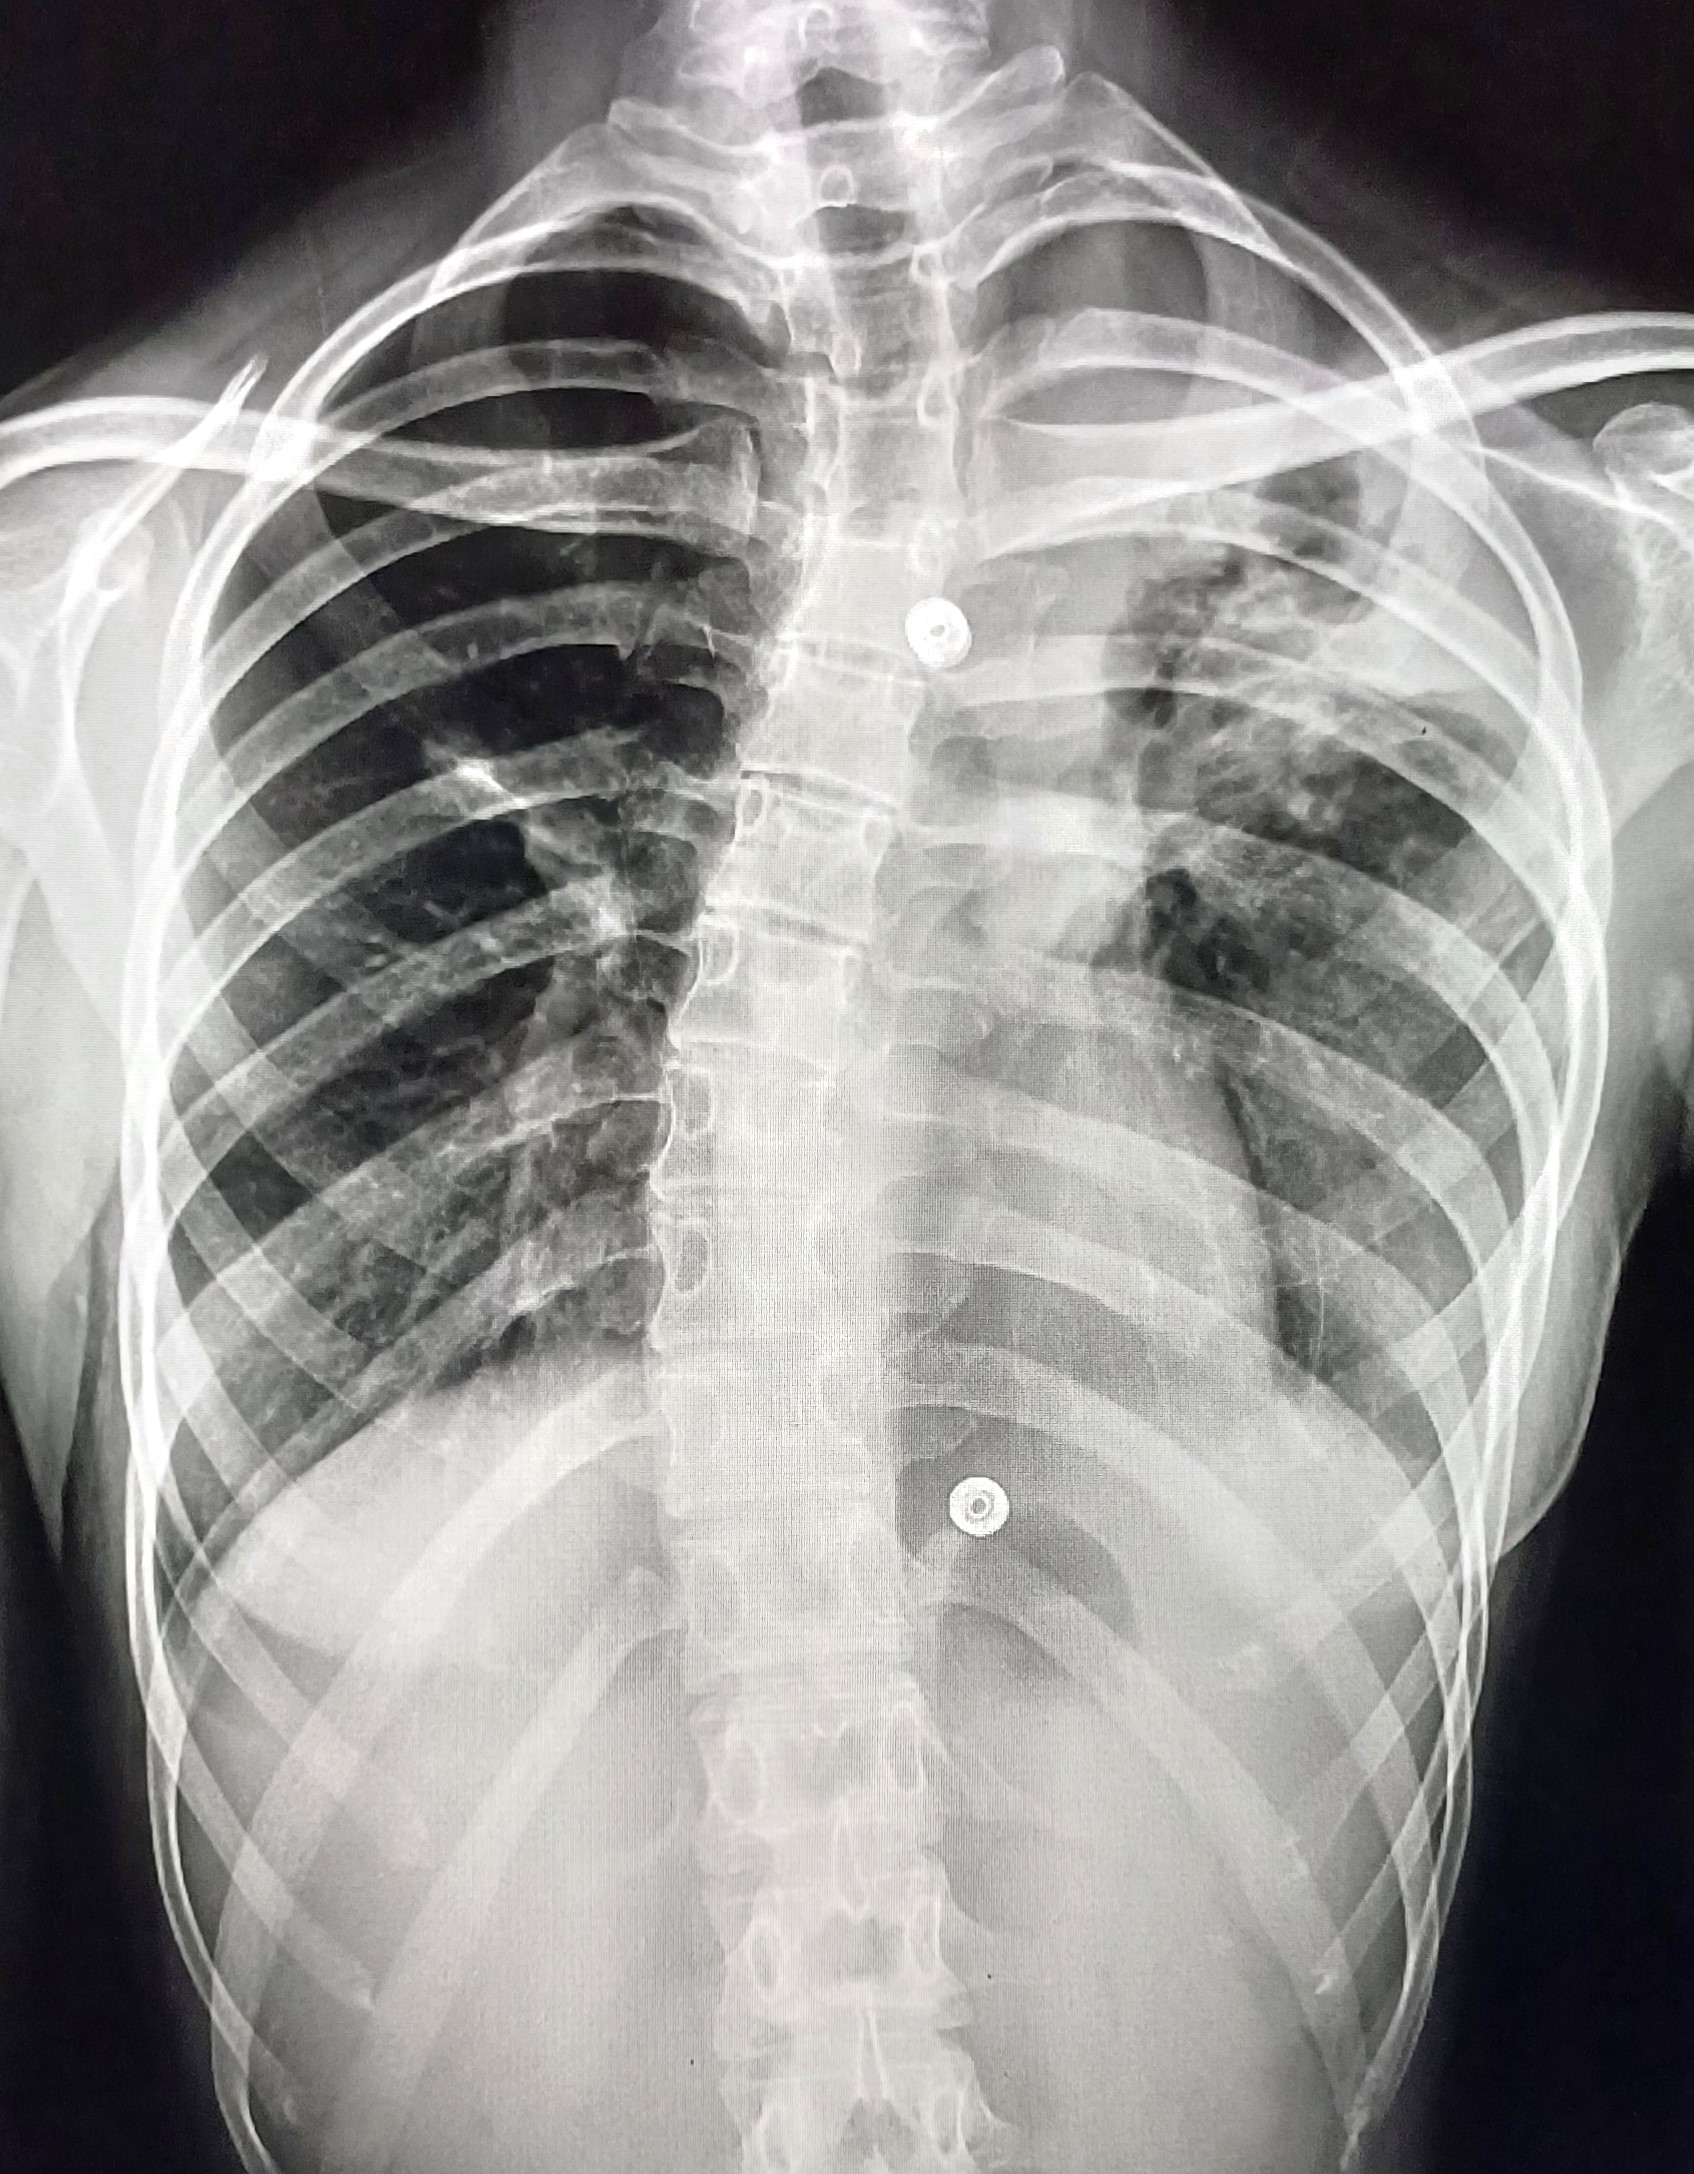

| 4 | IGGMC, Nagpur, Nagpur | P2 | 29-4468 | Moh. Salehuddin | Consent taken on Paper | 68 Yrs. |

Provisional Diag : Miliary TB?

Final Diag : Miliary TB |

TB Case (Confirmed) | Bilateral Infiltrate Query Miliary | Abnormality visible on x-ray |

View |